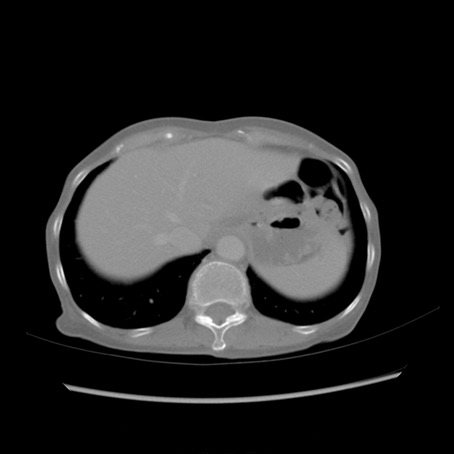

冠状断像

【症例】80歳代女性

【主訴】胸のつかえ感

【現病歴】約9時間前に食後から胸のつかえた感じあり、嘔吐あり、来院。

【既往歴】胃癌(全摘)、胆摘、虫垂炎

【身体所見】心窩部に圧痛あり、反跳痛なし。

【データ】WBC 5700、CRP 0.05